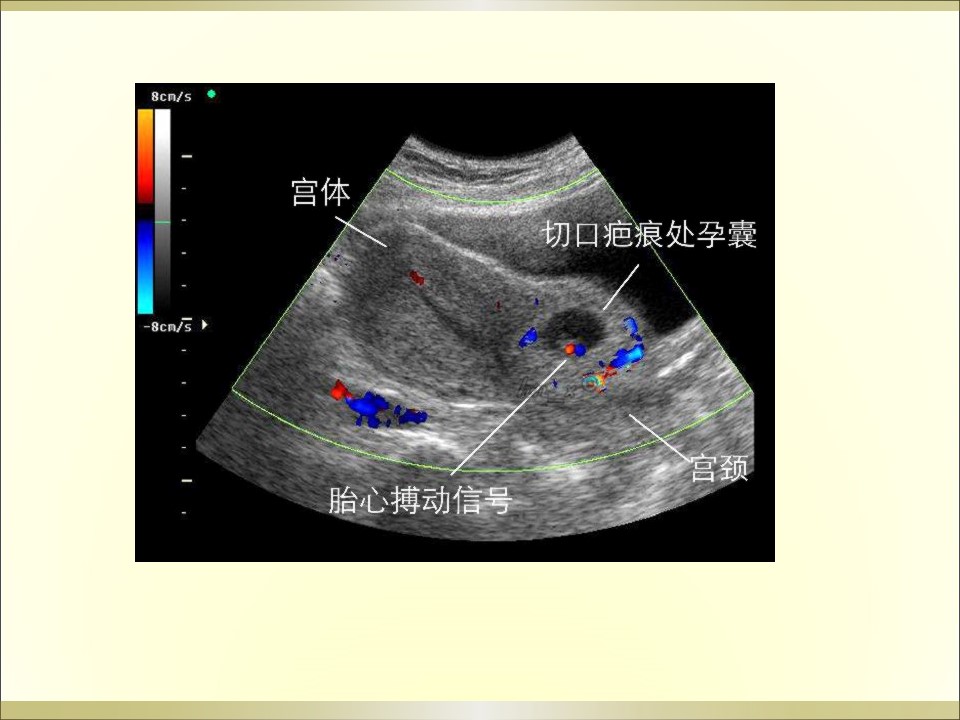

妇产科急腹症是指因妇科疾病引起的剧烈的急性腹痛,可以是原有疼痛突然加剧,或原无疼痛突然发生,是病因较多的常见病,特点是发病急、病变进展快、病情重,需要及时作出病因诊断及治疗。